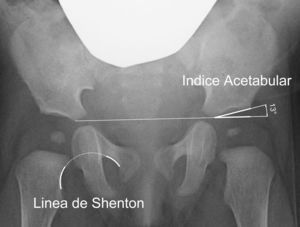

El índice acetabular que mide la oblicuidad del techo acetabular es la medida más utilizada para valorar la morfología acetabular, aunque su valor puede alterarse por la posición de la pelvis40 (fig. 2). El índice acetabular presenta un rango de valores considerados como normales. En general, se considera como normal los siguientes límites superiores: 30° en niños menores de un año; 25° en niños con una edad comprendida entre el año y los 3 años de edad; y 20° desde los 3 años de edad29. Algunos autores consideran patológico todo valor superior a 30°41. Sin embargo, el intervalo de confianza de la variación intraobservador es de ±6°; mientras que el intervalo de confianza de la variación interobservador es de ±5,5°42. Por ese motivo, se considera que la progresión del valor en una serie de radiografías tiene mas importancia que el valor absoluto de una medición aislada42,43.

Existen, además, otras medidas radiográficas que valoran la relación del fémur proximal y el acetábulo, como son la línea de Shenton, el ángulo centro-borde de Wiberg y la cobertura acetabular. La línea de Shenton es el arco formado por el borde inferior del cuello femoral y el borde superior del agujero obturador cuando la cadera se encuentra anatómicamente reducida (fig. 2). La línea de Shenton es la medida más ampliamente utilizada para valorar la relación entre el fémur proximal y el acetábulo, sobre todo a partir de los 2 años de vida40. El ángulo centro-borde de Wiberg refleja la cobertura de la cabeza femoral. En el adulto, los valores superiores a 25° son considerados normales, mientras que los valores inferiores a 20° se consideran patológicos. Sin embargo, entre los 3 y los 17 años de edad se consideran patológicos los valores inferiores a 15°44. El ángulo centro-borde de Wiberg presenta una gran variabilidad durante los primeros 3 años de vida debido a la dificultad para localizar el centro de la cabeza femoral44. En la subluxación de la cadera encontramos una línea de Shenton interrumpida y un ángulo centro-borde disminuido6. Por el contrario, la línea de Shenton está íntegra en la displasia acetabular, aunque el ángulo centro-borde está igualmente disminuido. En la luxación de cadera, la línea de Shenton queda interrumpida al estar la cabeza femoral luxada posterosuperiormente; mientras que no es posible calcular el ángulo centro-borde.